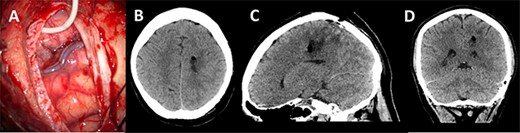

A post-operative CT head was performed within 24 h of surgery documenting collapse of the surgical tract (Fig. 5). The patient did not have any post-operative deficit and was discharged home. Histopathology confirmed a Glioblastoma Multiforme.

Post-operative imaging; (A) post-decannulation brain surface after transsulcal approach; (B–D) axial, sagittal and coronal CT images showing collapse of the surgical tract and no overt complications.